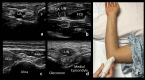

Neuromuscular ultrasound (NMUS) is becoming a standard element in the evaluation of peripheral nerve and muscle disease. When obtained simultaneously to electrodiagnostic studies, it provides dynamic, structural information that can refine a diagnosis or identify a structural etiology. NMUS can improve patient care for those with mononeuropathies, polyneuropathy, motor neuron disease and muscle disorders. In this article, we present a practical guide to the basics of NMUS and its clinical application. Basic ultrasound physics, scanning techniques and clinical applications are reviewed, along with current challenges.